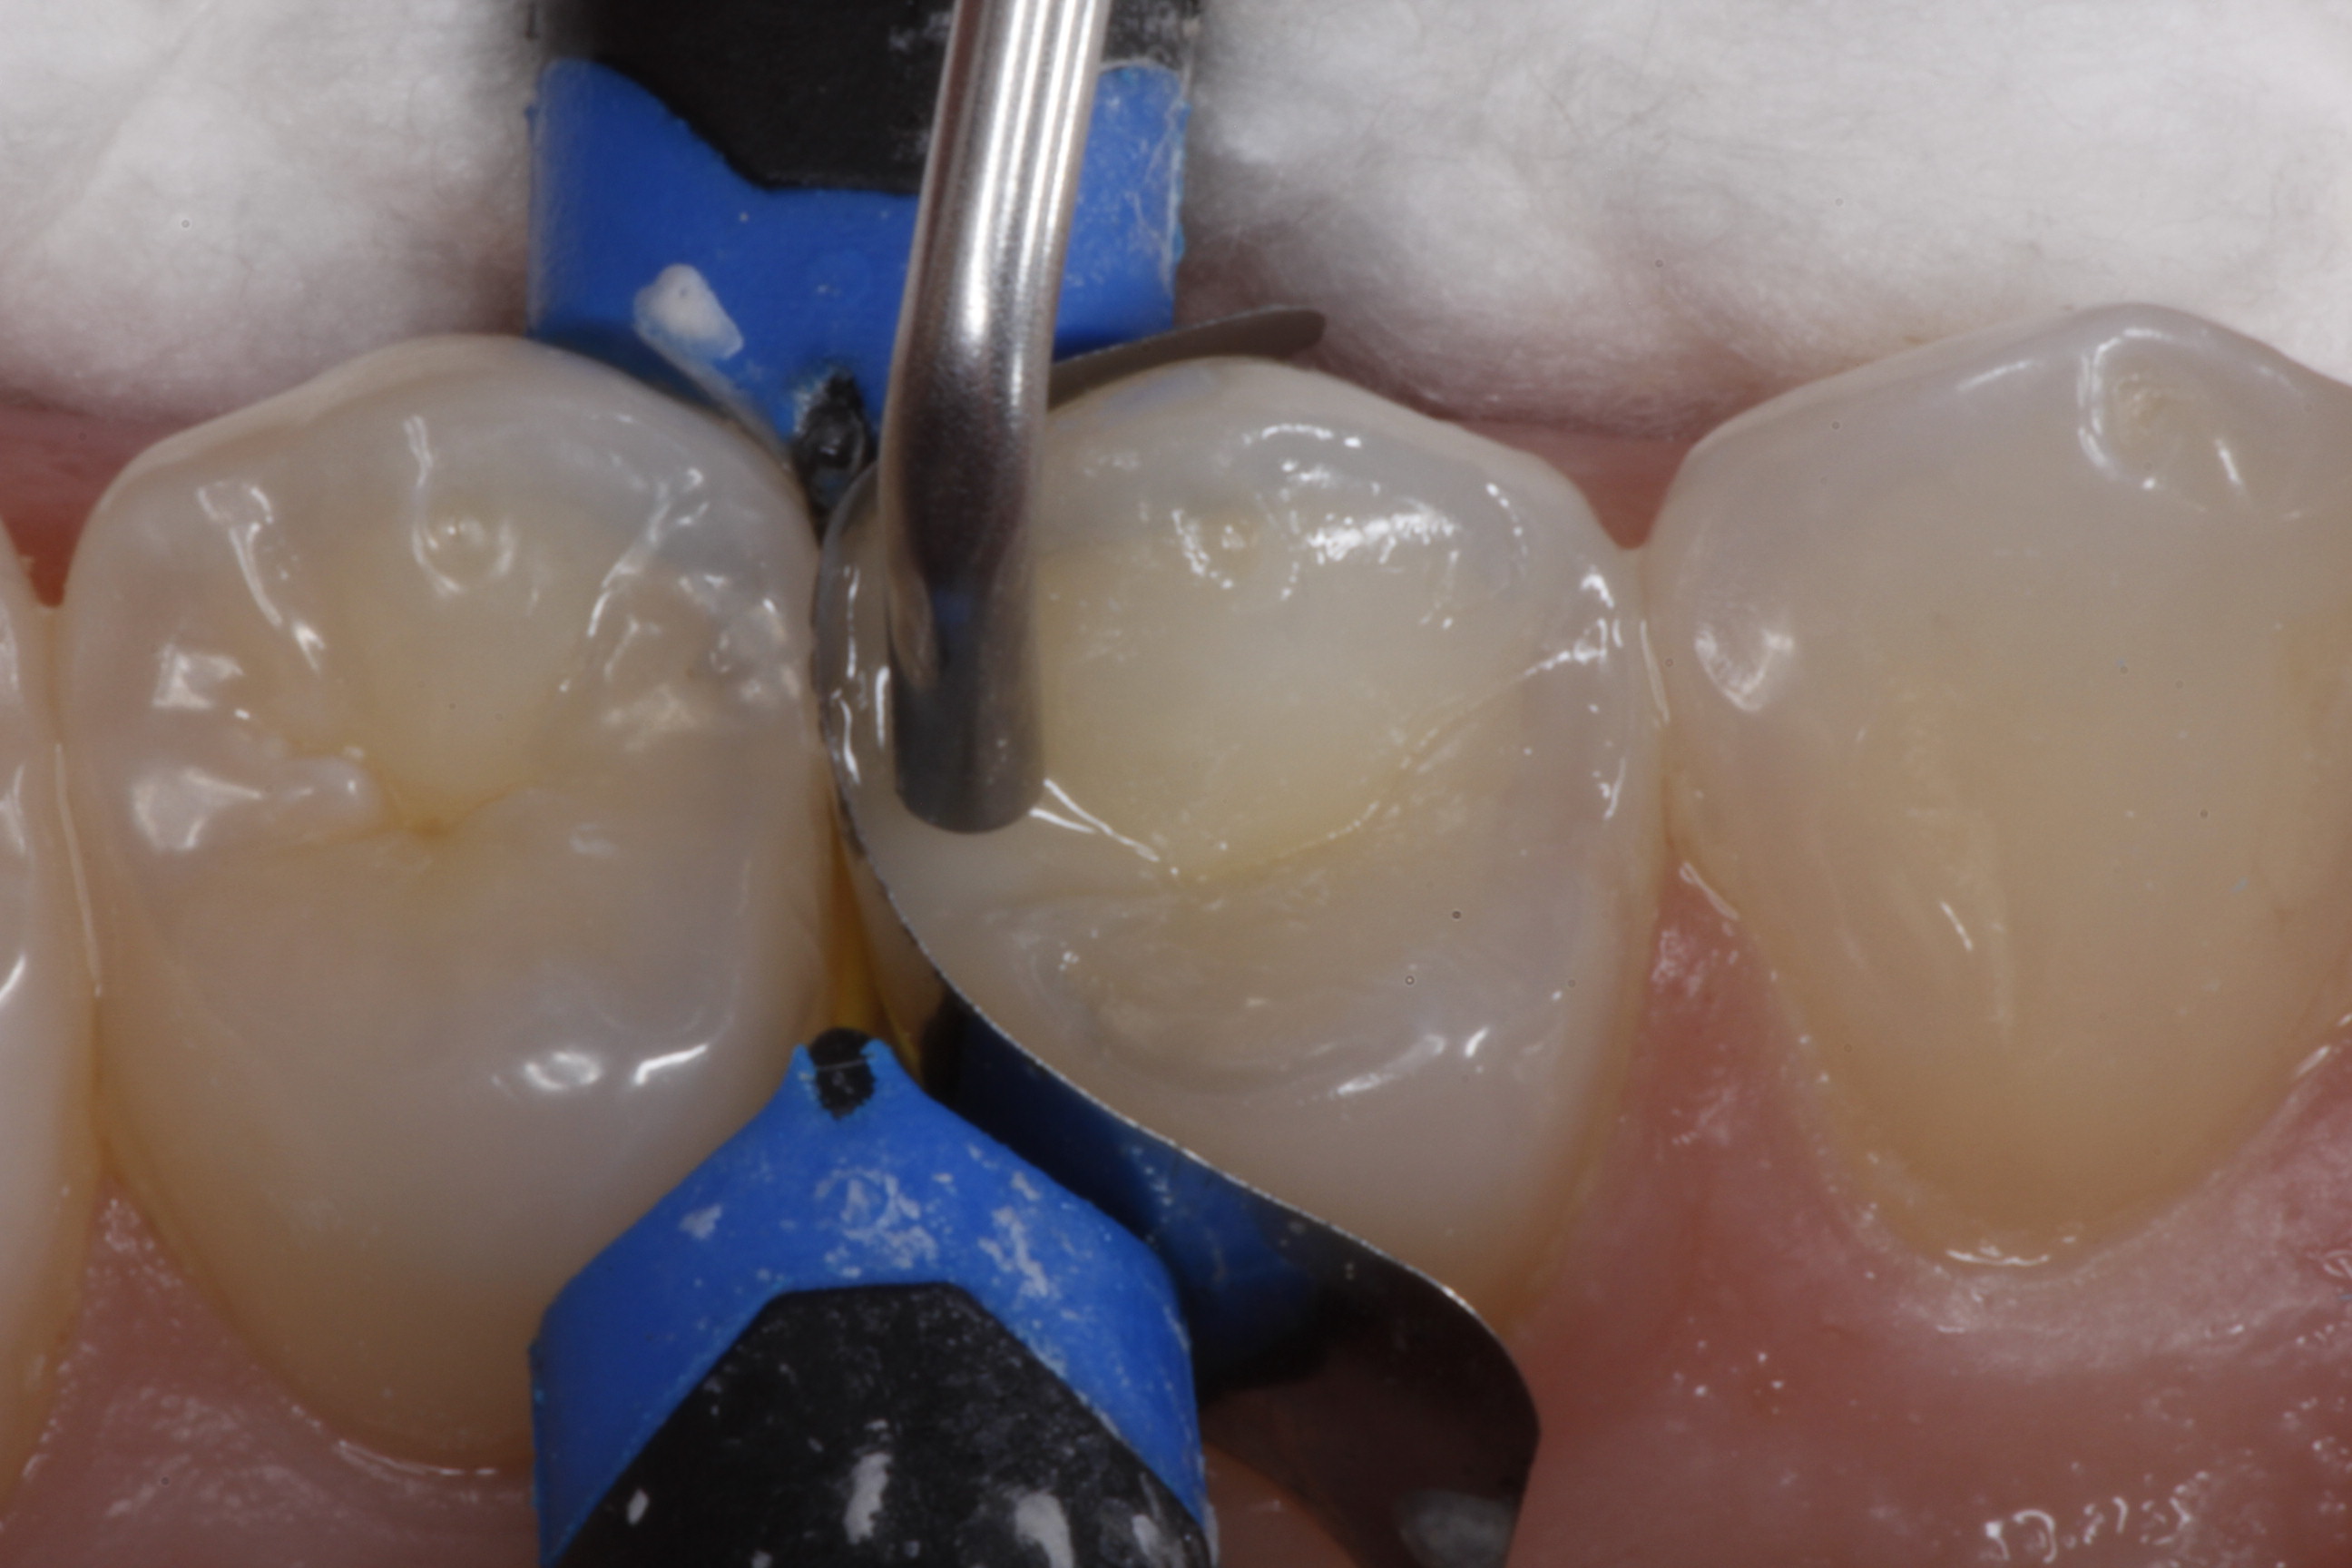

Fig 8. After isolation, a sectional matrix is placed to restore contact and proximal anatomic form to the composite to be placed. The goal is to perform as little rotary finishing and polishing as possible by having the matrix fit precisely to the cavity margins.

Figure 8